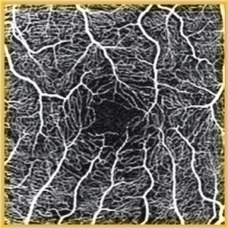

- CT-Angiographyにより、非侵襲で網膜毛細血管を各層別に観察可能(オプション)

12×9mmの撮影範囲内で2種(3/4.5mm)のパノラマ合成を自動でおこなうことが可能です。

スキャン位置は順次移動するため、固視位置を変更することなく撮影できます。

任意設定により5種類(初期設定:網膜全層、表層、深層、外層、脈絡膜)のパノラマが同時に自動合成できます。

網膜全層 HD4 4.5×4.5mm 6枚 パノラマ |

網膜表層 |

網膜深層 |

網膜外層 |

脈絡膜 |